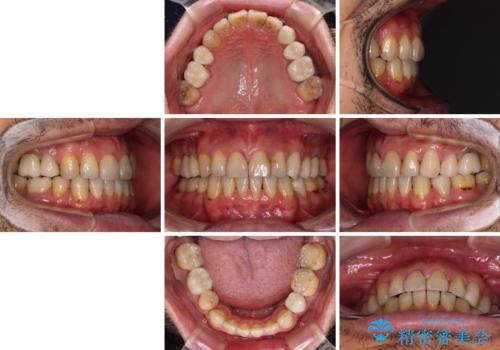

- むし歯による奥歯の痛みを気にして来院された患者様です。

神経にまでむし歯の及んでいる歯や、既に根管治療がされている歯に痛みがあったため、まずは根管治療を行うこととしました。

その後、以前行った抜歯矯正の後戻りをインビザライン・ライトにより改善し、むし歯や銀歯はオールセラミッククラウンにて補綴治療することとしました。

痛みは速やかに引き、銀歯や黒く変色したむし歯がセラミッククラウンで自然な色合いに仕上がり、患者様には大変満足していただきました。